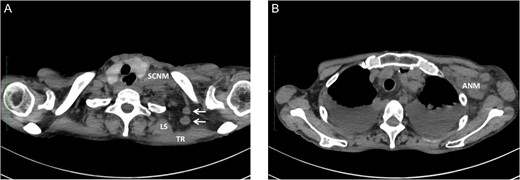

We have had three cases of this unusual LNM from cancer of the thoracic esophagus to date. Clinicopathological characteristics and survival are presented in Table 1. This unusual LNM developed after esophagectomy in two patients (cases 1 and 2, Fig. 2) and was found at presentation in a third patient (case 3, Fig. 3).

Metastasis of the supraclavicular nodes (SCNM), the nodes located between TR and LS (arrow) (A), and the axillary nodes (ANM) (B) developed 4 months after esophagectomy.

One possible explanation of this phenomenon is retrograde spread from SCNM. Komatsu et al. [3] reported four cases of axillary node metastasis (ANM) of squamous cell carcinoma of the upper- and mid-thoracic esophagus. All ANM developed on the left side, with the preceding or simultaneous left SCNM. The supraclavicular nodes are well known as regional lymph nodes in breast cancer, and lymphatics from the axillary nodes are considered to communicate with the supraclavicular nodes. Based on experimental and clinical observations, they concluded that ANM might be caused by retrograde flow owing to lymphatic blockade by SCNM in esophageal cancer [3, 4]. A similar mechanism was speculated in our cases 1 and 2, in which preceding or simultaneous ipsilateral SCNM also developed. Interestingly, simultaneous ANM was also seen in case 2.